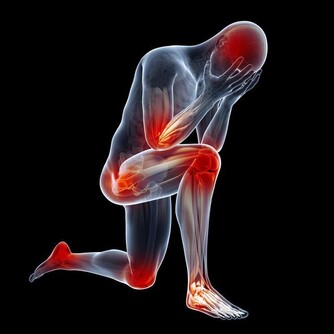

免疫力是人體自身的防禦機制,一個人免疫力低下,就很容易生病,也很容易傳染上疾病。

反之,免疫力好的人一般會擁有好的抵抗疾病的能力,這類人一般身體會比較健康,所以,我們應該提升自己的免疫力,提升自己的身體素質。

(1)經常出現輕微的身體不適,如頭疼、牙疼、嗓子疼,或渾身萎靡不振。

(2)平均每月或每兩個月生病一次,包括感冒、發燒、腹瀉等。

(3)近年來開始對某些事物(例如霧霾天氣、貓毛或狗毛)過敏。

(4)上班或者坐地鐵,如果旁邊有人咳嗽、大噴嚏,就很容易被傳染。

(5)換季節時很容易身體不適。

(6)經常臉上長疙瘩,或者口腔潰瘍。

(7)月經不調,或者經期易生病。

(8)經常神經衰弱,異常煩躁、鬱悶,或者夜間稍有動靜就睡不著覺。

免疫力較強的人,上述狀況可能一項也不會出現。而如果你超過3項都符合,那就說明你的免疫力現狀堪憂,有待提升!